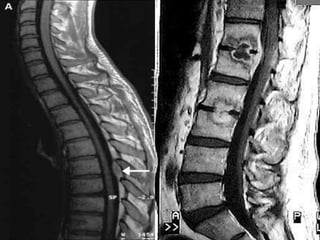

Imaging studies

Spinal MRI is the procedure of choice

(sensitivity 95%, specificity 92%).

Gadolinium enhancement increases sensitivity

and enables better differentiation between

abscess and surrounding neurological

structures.

Imaging studies Plain radiographsoccasionally demonstrate osteomyelitis but are of almost no utility. Spinal MRI is the procedure of choice (sensitivity 95%, specificity 92%). Gadolinium enhancement increases sensitivity and enables better differentiation between abscess and surrounding neurological structures. CT-guided needle aspiration may be used to obtain material for analysis.